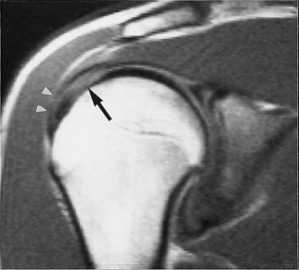

МРТ плечевого сустава. Т2-взвешенная корональная МРТ. Разрыв вращательной манжеты. Цветовая обработка изображения.

При МРТ плечевого сустава косвенным признаком разрыва вращательной манжеты служит высокий сигнал на Т2-взвешенных от поверхности сустава до субакромиальной (субдельтовидной) сумки. Частичные разрывы чаще всего по передней поверхности сухожилия м.supraspinatus, реже примыкая к большой бугристости или сухожилия м. infraspinatus.

МРТ плечевого сустава. Т2-взвешенная корональная МРТ. Субакромиальное скопление жидкости - косвенный признак разрыва вращательной манжеты.